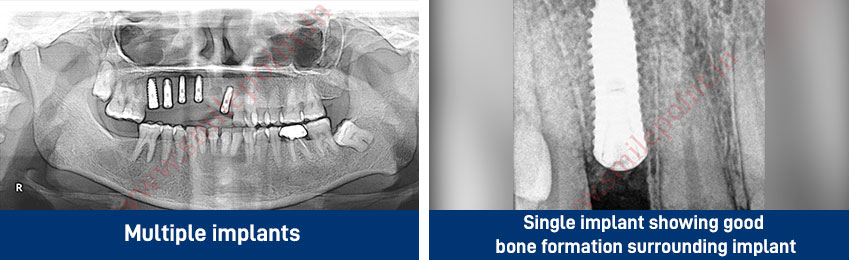

Dental Implants